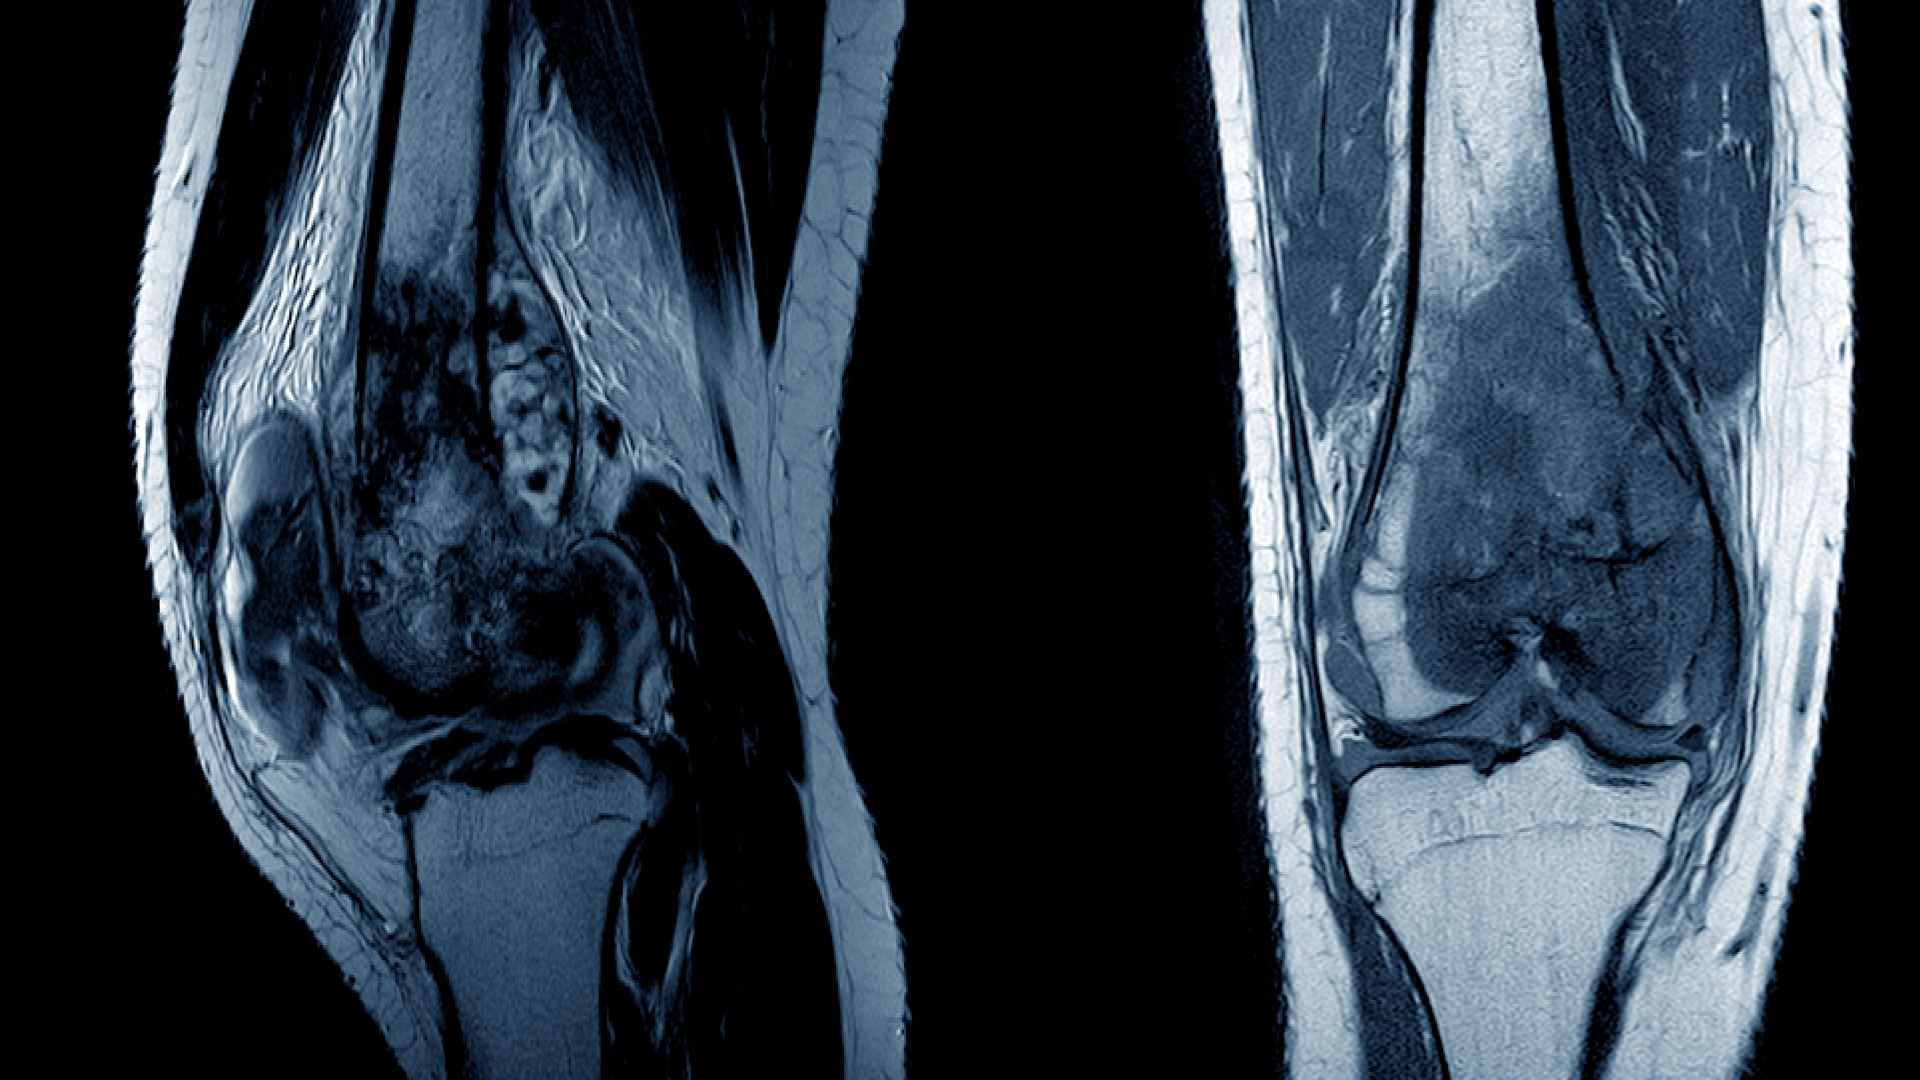

Osteosarkoma (kanker tulang) pada anak adalah tumor primer tulang belakang yang kerap dijumpai pada remaja. Kanker tulang ditandai dengan adanya sel-sel mesenkim ganas yang memproduksi osteoid atau sel tulang imature.

Kanker tulang terjadi karena sel-sel pembentuk tulang mengalami mutasi. Mutasi tersebutlah yang mengakibatkan sel-sel pembentuk tulang memproduksi tulang baru meski tak dibutuhkan. Akibatnya, tulang baru tadi berubah menjadi tumor dan menyerang bagian tubuh yang lain.